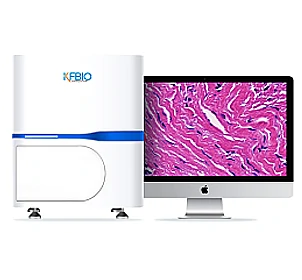

Digital Pathology Slide Scanner (PRO)

Digital Pathology Slide Scanner (PRO)

K-Viewer, a slide viewing software developed by KFBIO, allows pathologists to review and annotate digital slides for ease of diagnosis. It enables pathologists to swiftly access slides or cases on the desktop or remotely via the computer, smartphone, or tablet device.

High Image Quality for Digital Pathology

KFBIO Digital Pathology Slide Scanner (PRO) is a world leader in the accuracy of movement, focus, and image processing, and its accurate whole slide imaging not only meets the requirements of digital slide viewing and operation but is also suitable for AI-assisted image analysis.